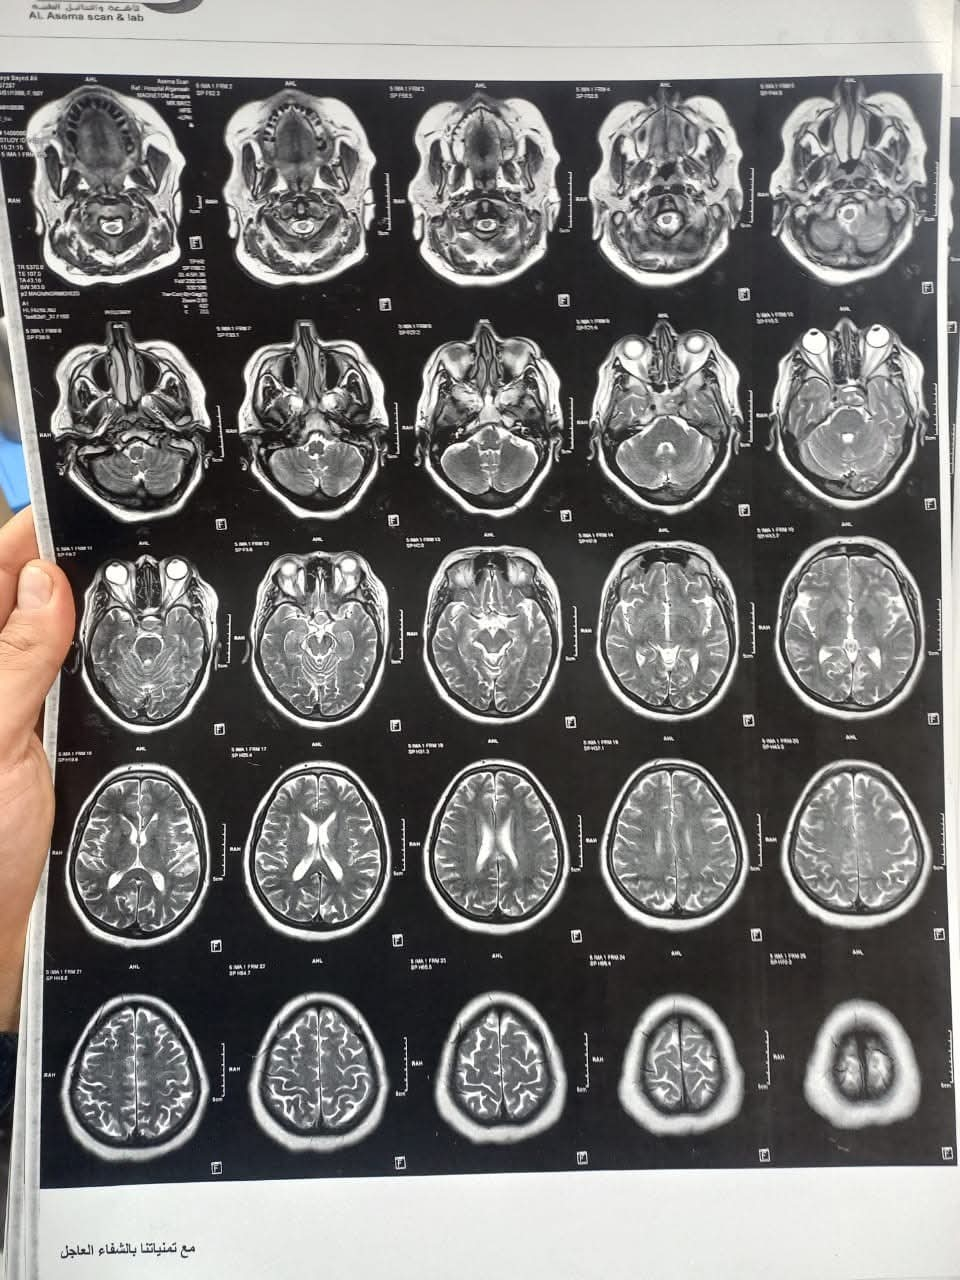

نجح فريق طبي مشترك من قسمي جراحة الأنف والأذن والحنجرة وجراحة المخ والأعصاب بمستشفى بني سويف الجامعي، في إجراء جراحة دقيقة لاستئصال ورم بالغدة النخامية لسيدة في العقد الخامس من العمر، باستخدام المنظار الأنفي الضوئي دون الحاجة إلى إجراء جراحة خارجية.